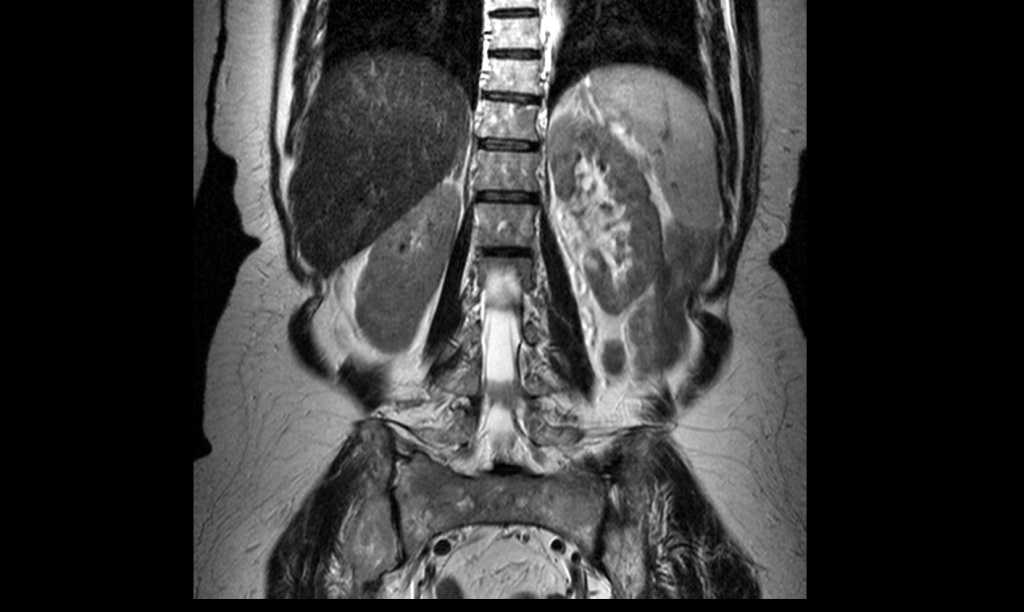

На снимке МРТ хорошо видно мышцы и костную ткань

- МРТ и компьютерная томография. Позволяют узнать о состоянии мягких тканей спины в области локализации боли.